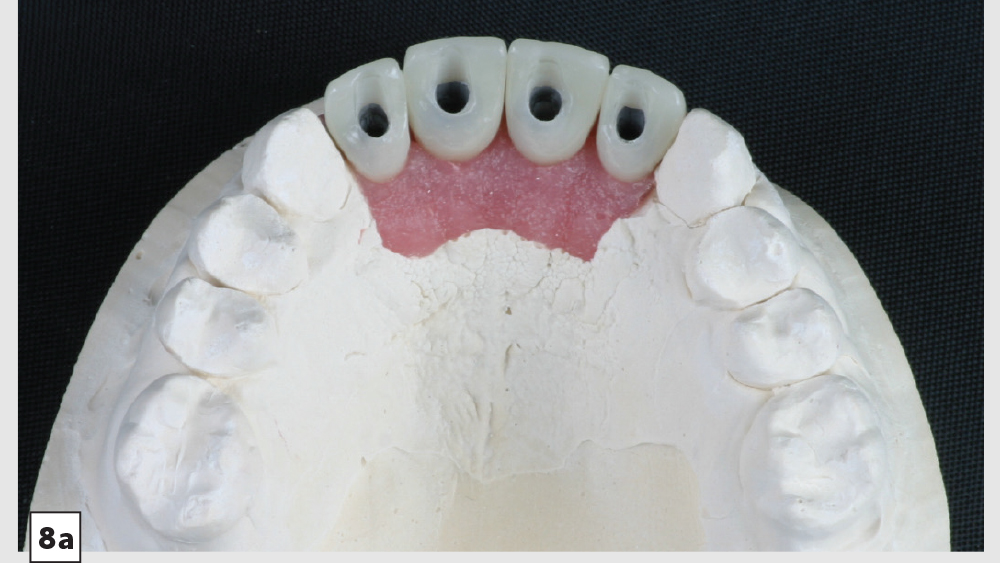

Digital treatment planning (DTP) with the team at Glidewell Laboratories allows me to ensure that implants are precisely placed, with full consideration given to the desired esthetics of the final restorations. But there was another unique element involved in planning the case described below: While it was esthetics that caused the patient to seek treatment, his career as a glass blower required his implants to be placed in functionally ideal positions. The potential complexity of these multiple requirements solidifed my decision to approach his case with implant positioning predetermined via DTP.

This patient came to me with four missing anterior teeth in positions #7–10. He had been missing these teeth for some time and was wearing a temporary denture to address the cosmetic issue this created. When he came to my practice, he was in a financial position to solve the problem permanently with implant restorations. Based upon the anterior space available and the fact that the patient’s surrounding tissue was in good health, I chose to move forward with Hahn™ Tapered Implants and BruxZir® Esthetic restorations.